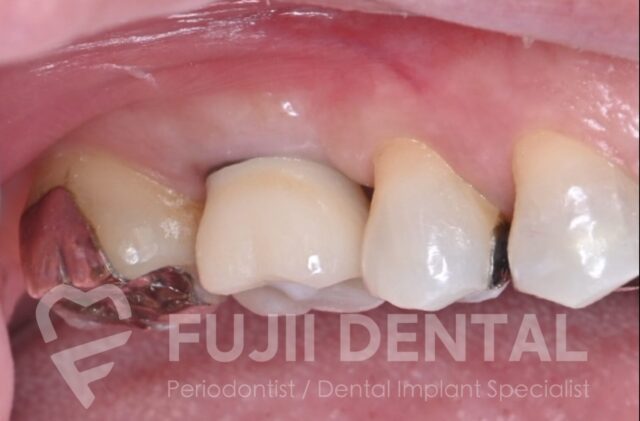

左上の後ろから2番目の奥歯(第一大臼歯)が割れ、歯の周りの組織が膿んで歯肉に穴が空いていました。この歯を残すことはできません。一方、レントゲンでは、一番奥の歯(第二大臼歯)に大きな歯石が付着し、歯周ポケットは8mm。骨の半分近くが失われている重度歯周病でした。

治療計画としては、2本抜歯してインプラント治療を行う選択肢も考えられましたが、後方の第二大臼歯は歯周病治療を行って残す方針としました。

術後 3ヶ月後。骨がしっかりできていますので、もとの歯の形に近くなる太いインプラントを入れられます。また、8mmあった深い歯周ポケットが3mmと浅くなっており、歯周病は治癒したといえます。

最終的な補綴物(被せ物)を装着した状態です。8mmあった歯周ポケットは正常値の3mmへと治癒し、抜歯と手術回数を最小限に抑えながら、歯周病を治し、しっかり噛める状態を回復しました。